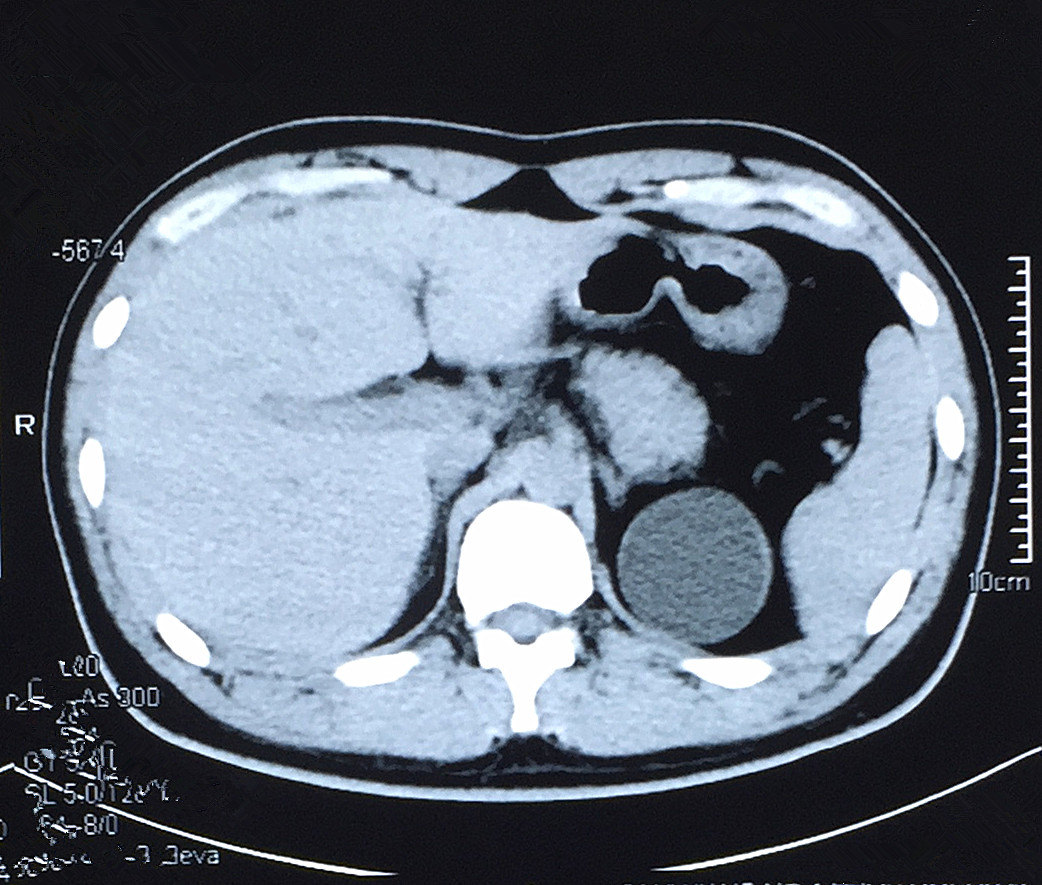

患者男,62岁,体检发现左肾囊肿6.5×5

ct所见:右肾囊肿.

右肾囊肿ct